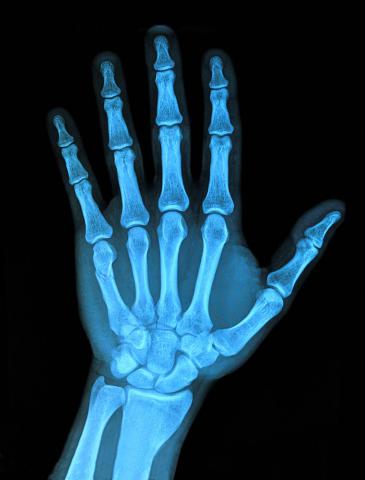

X射线

X射线是19世纪末20世界初物理学的三大发现之一,在发现X射线后仅仅几个月的时间内就被用于医学成像检查。X射线诊断是目前最重要的诊断方法,我们经常听说过的胸透、拍胸片、CT检查都属于X射线诊断的范畴。由于X射线对不同密度物质的穿透性有差异,我们通过X射线诊断能够发现身体内部的疾患。

手部X片